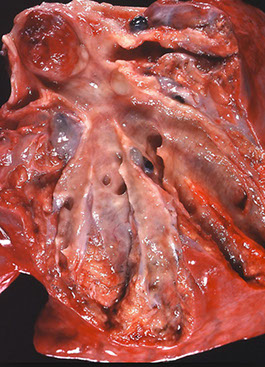

Emphysema - note the bullae and blebs, anthracosis, and that the lungs almost meet in the midline